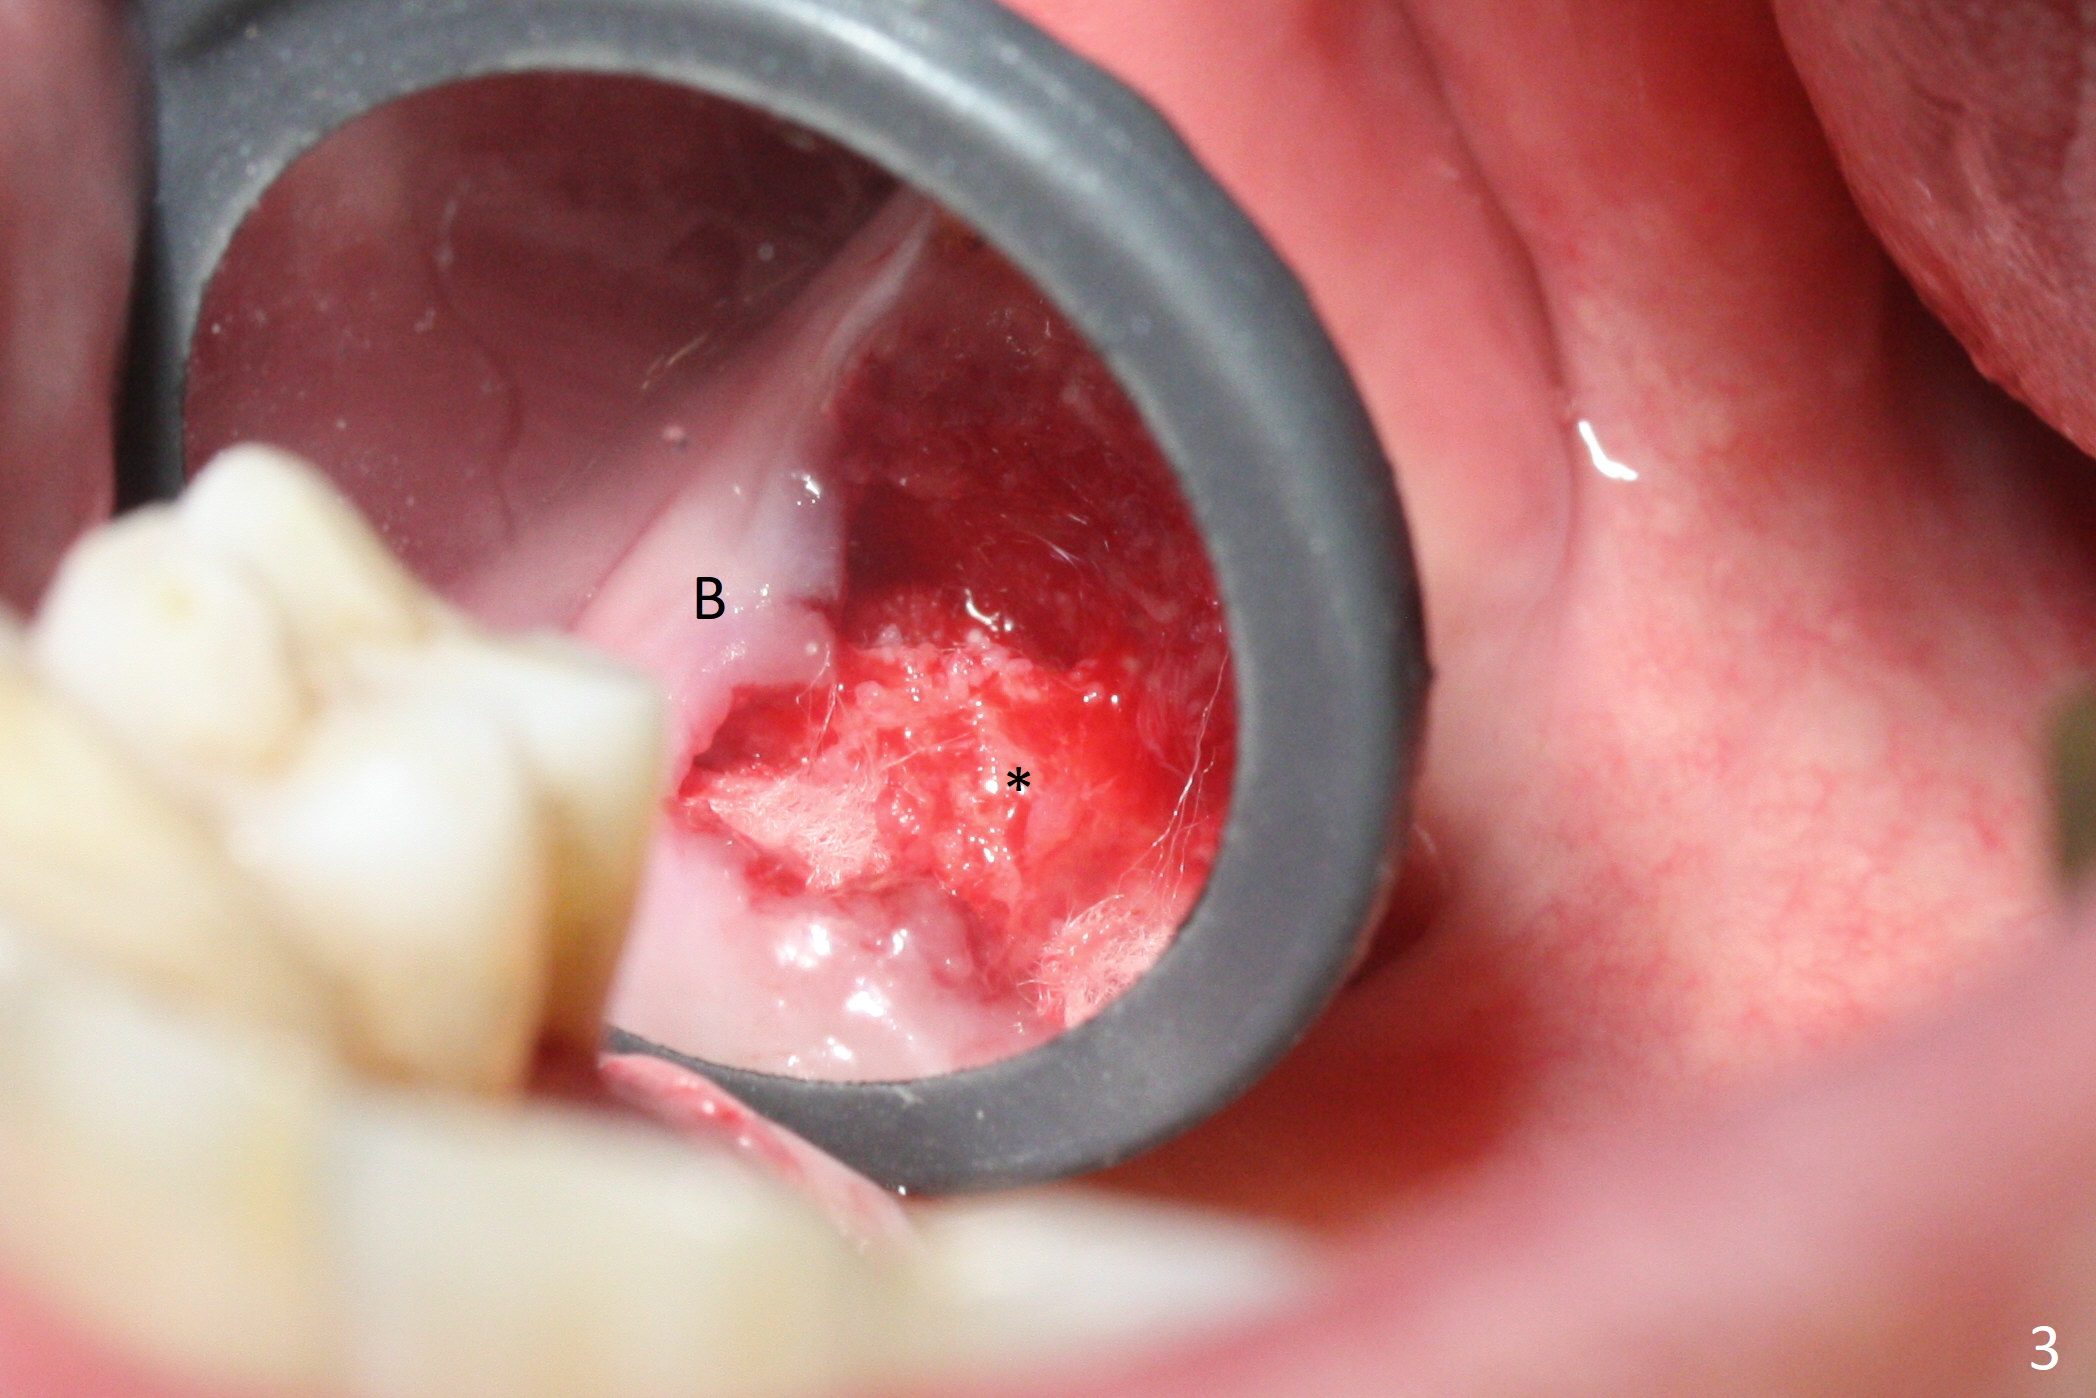

Buccal gingival recession at #14 (Fig.1) is less severe than the palatal one (Fig.2).  Without raising the buccal gingiva (Fig.3 B), osteotomy in the septum is established apparently in the middle socket (Fig.3 *, 4).  As the osteotomy increases with 3.8 mm drill, the palatal wall of the osteotomy starts to be perforating.  When a 4.5x11.5 mm implant is placed, palatal threads are exposed, to which autogenous bone and Vera Graft are placed (Fig.5 *).  After placement of a 5.5x5(3) mm abutment, an immediate provisional (Fig.6 P) is fabricated to cover the sockets.  If the septal dimension were studied carefully by raising the buccal gingiva slightly, the osteotomy could be initially more buccal so that the palatal thread exposure could be less.  When the provisional is removed 1.5 months postop, the implant is exposed palatally.  The margin of the provisional is modified so that the implant can be cleaned by the patient using Water Pik.  In fact, the healthy gingiva seems to be attached to the implant threads 2 weeks later (Fig.7).  The distal implant threads remains exposed 6 months postop; it appears that the distal socket wall has resorbed (Fig.8).  The sockets heal 1 year 7 months post cementation (Fig.9).